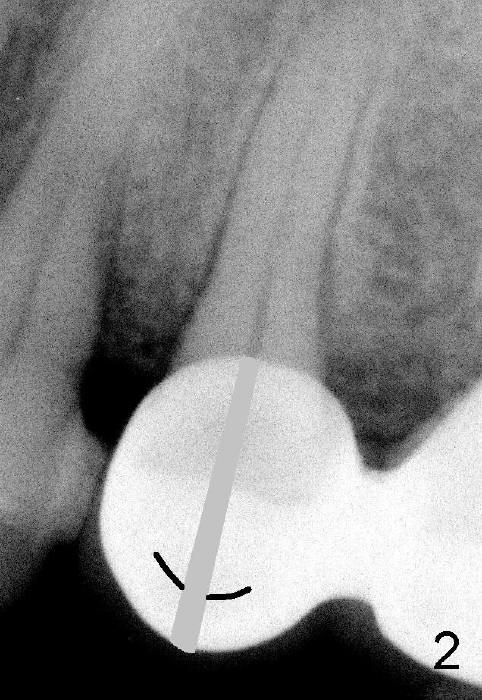

倪先生左上有一个PFM(porcelain fused to metal)悬臂桥(图一:5-7),五号牙有根尖阴影(*),需要做根管治疗。本来应该撤桥,五,六号牙都需要做根管治疗(六号牙根管治疗不全),七号牙植牙。但是病人不想那么麻烦,好了,我们先做五号牙根管治疗。